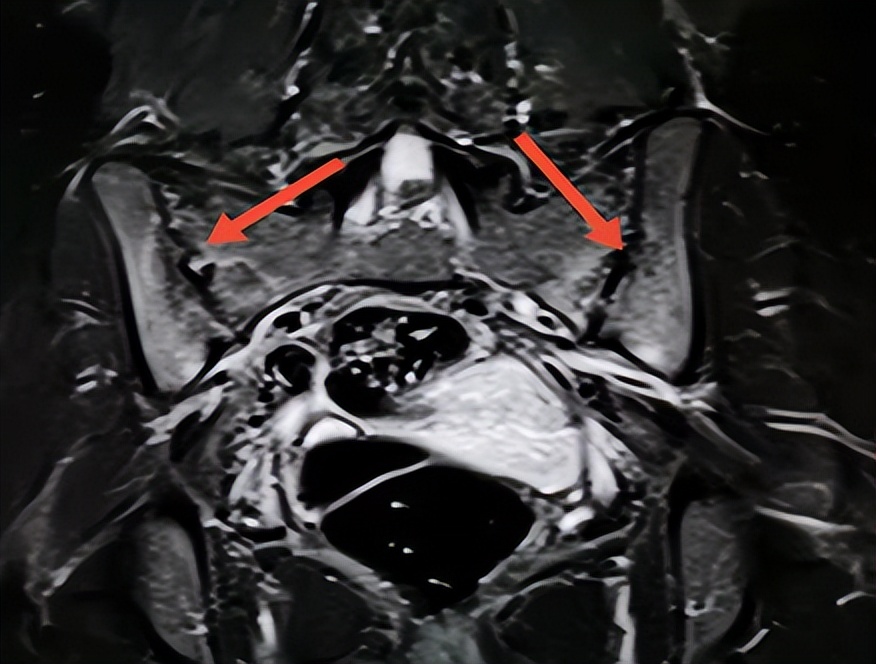

近日,经多方打听,她在丈夫的陪同下来到郑州市管城中医院骨伤科求医。郑州市管城中医院副院、骨伤科首席专家王长勇接待了刘女士,那天,年轻貌美却显憔悴的她,弯腰驼背、一瘸一拐地来到诊室。王院长检查她的 脊柱已处于僵直状态,无法平躺 ,完全不能直立靠墙, “4字试验”明显阳性,这时王院长心中已经有谱, 当即为她做腰椎MRI、骶髂关节MRI、炎症指标等相关检查。果然,不出所料,折磨她这么久的病根水落石出——强直性脊柱炎(“强直”)。

强直性脊柱炎(AS)俗称驼背,是一种以骶髂关节和脊柱附着点炎症为主要症状的慢性炎症性疾病,除了中轴关节以外,全身其他脏器也可以受累,包括眼睛、心血管、胃肠道、皮肤都是它受累的部位,所以说它 是一种全身性的疾病 。

屁股痛在 早期多是一侧开始 ,几个月后发展为双侧屁股的持续性疼痛,之所以会屁股疼是强直性脊柱炎出现肌腱和韧带附着点的 炎性改变 ,当累及坐骨结节、耻骨联合、髂骨结的时候,就会出现相应部位的炎症表现也就是疼痛(如臀部疼痛、足跟痛)。